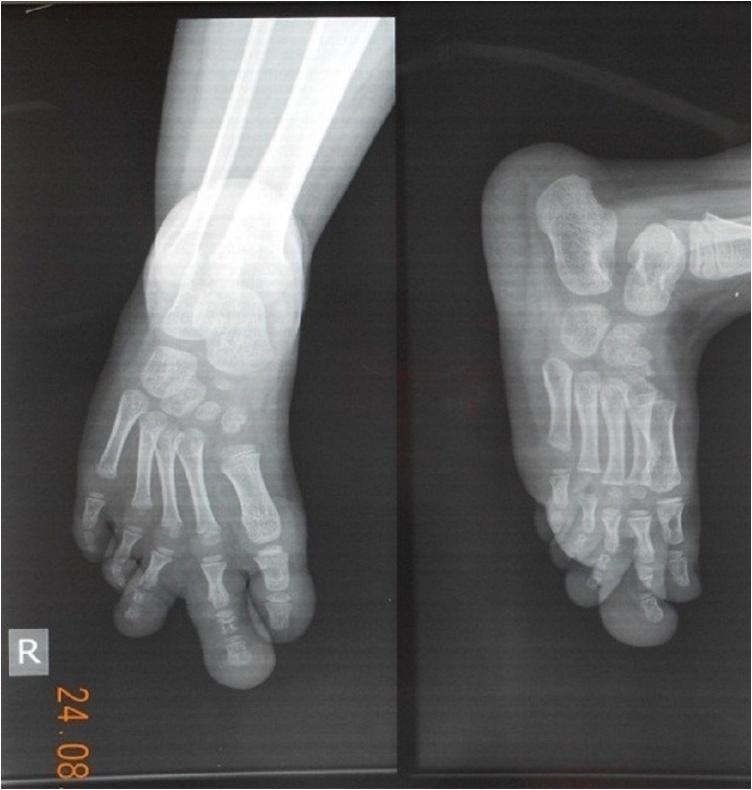

We report a three-year-old female patient presenting with an enlargement of the right foot index and middle toes. The anomaly was noticed at two months of age and grew progressively. X-ray imaging revealed enlarged bones and soft-tissue hypertrophy proximal to the distal phalanx of the second and third digits. There was no history of other systemic or syndromic diseases. The patient underwent phalangectomy surgery involving reduction of the fibrofatty tissue, double-pedicle medial and lateral digital artery flap. Satisfactory results were noted at evaluation two months of after surgery.

我们报告一名3岁女性患者,其右足示趾和中趾增大。该畸形在患儿2个月大时被发现,并逐渐发展。X线成像显示第二和第三趾远节指骨近端骨骼增大及软组织肥厚。无其他全身性或综合征性疾病史。患者接受了包括减少纤维脂肪组织的指骨切除术及双蒂内外侧指动脉皮瓣手术。术后2个月评估时效果满意。